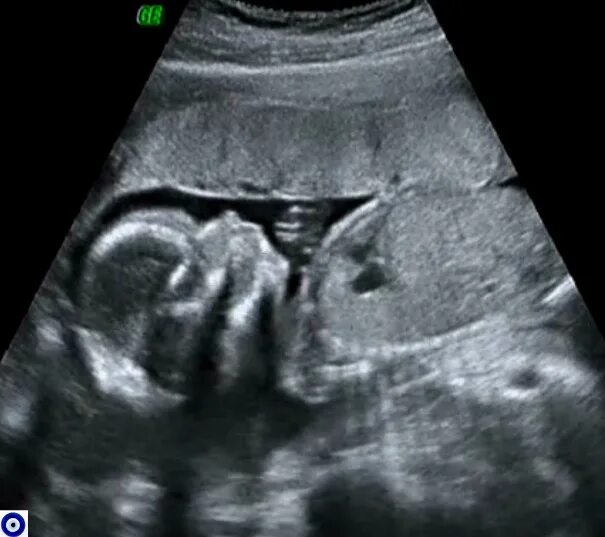

Второй скрининг 21 неделе